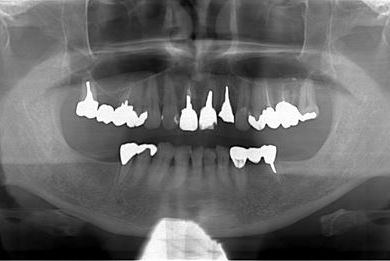

インプラントの症例写真 IMPLANT

| 性別/年齢 | 男性 / 61歳 | ||||||||||||||||||||||||||||||||

| 主訴 | 奥歯のインプラント治療を希望。 | ||||||||||||||||||||||||||||||||

| 治療内容 | インプラント4本、メタルボンドセラミッククラウン4本 | ||||||||||||||||||||||||||||||||

| 総治療費 | 1,508,220円 | ||||||||||||||||||||||||||||||||

| 治療期間 | 7ヶ月 |